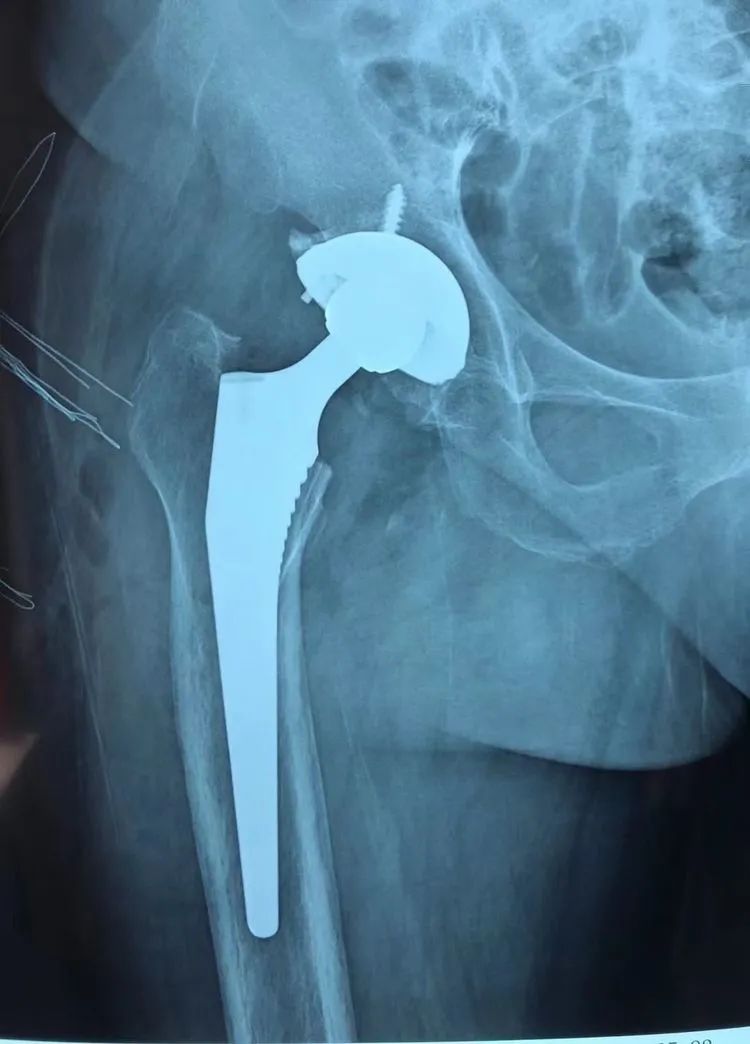

家住壽縣的馬大娘,十五年前開始出現(xiàn)雙側(cè)髖關(guān)節(jié)疼痛,隨著時(shí)間的推移,疼痛越來越厲害,腿不能屈,蹲也蹲不下。經(jīng)人推薦,馬大娘一家來到了淮南東方醫(yī)院集團(tuán)廣濟(jì)醫(yī)院骨科就診。完善檢查后,明確診斷為“雙側(cè)先天性髖關(guān)節(jié)發(fā)育不良(DDH)、雙側(cè)股骨頭無菌性壞死”,骨科王懷波主任邀請(qǐng)廣濟(jì)骨科首席專家方成教授共同開展術(shù)前討論,迅速為其擬定“右側(cè)全髖關(guān)節(jié)置換術(shù)”。

隨后,在手術(shù)室團(tuán)隊(duì)的配合下,為其行腰硬聯(lián)合麻醉下“右側(cè)全髖關(guān)節(jié)置換術(shù)”,方成教授主刀,王懷波主任協(xié)同,熟練地切開、顯露,切除、清理、安裝......手術(shù)十分順利。